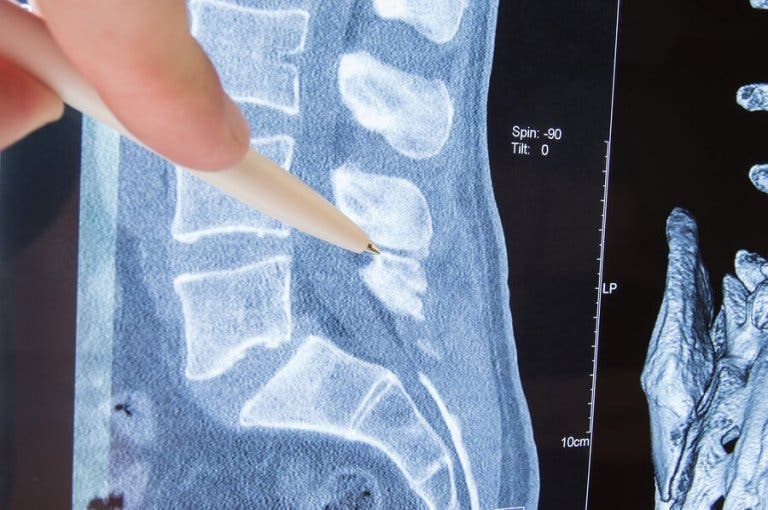

Гръбначният стълб е костна структура изградена от прешлени, които предпазват костите и ви позволяват да се движите свободно. Прешлените имат отвори от всяка страна, през които преминават нервите отиващи към различни части на тялото.

Тази част от нерва, която излиза от прешлена се нарича “корен на нерва”. Радикулопатията представлява притискане на нерва, и по-точно на корена на нерва. Какво води до това? Какви са клиничните симптоми на заболяването? В тази статия ще ви отговорим на тези въпроси и ще ви дадем информация за съществуващите варианти на лечение.

Лумбална радикулопатия

Засяга лумбалната част на гръбначния стълб. Нервите в тази област контролират мускулите и чувствителността на кожата на задните части, бедрата ходилата. Затова пациентите имат оплаквания в долната част на гърба, бедрата, краката и ходилата.

В най-тежките случаи контролът на сфинктера е нарушен. Ако притискането се появи на изхода на седалищния нерв, най-често срещаният симптом е болката обхващаща долната част на гърба до петите на краката, в задната част на крака. Това заболяване е познато като ишиас.